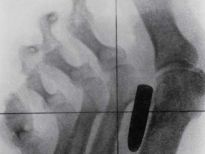

Bu röntgenler gerçek!

Bu röntgenler gerçek! galerisi resim 1

İki çatalı, bir tükenmez kalemi ve diş fırçasını yutmuş bir hasta.